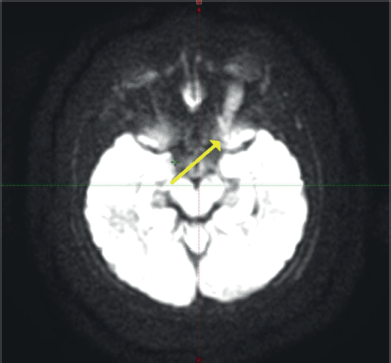

Contrast-enhanced magnetic resonance imaging (C-EMRI) of the brain and orbit done on 5 June 2023 showed diffuse fusiform enlargement of the left optic nerve measuring (35 × 12 × 11) mm as illustrated in Figure 1. There was involvement of the entire intra-orbital segments of the left optic nerve. The lesion was T1 hypointense and T2 hyperintense. Left proptosis was noted with no extension to the optic chiasm or contralateral optic nerve. The brain parenchyma was unremarkable.

Figure 1. MRI of the brain and orbit showing an enlarged left optic nerve (yellow arrow).